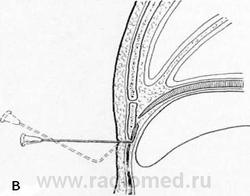

Дивертикулы перикарда, сохраняющие связь с полостью сердечной сорочки при посредстве шейки, через просвет которой жидкостью свободно перемещается в обоих направлениях, обычно имеют грушевидную форму. Суженная часть тени дивертикула соответствует его шейке, направляющейся к перикарду. Эта конфигурация дивертикула, его шейка и соотношения с перикардом определяются лишь в условиях пневмомедиастинума. На бесконтрастных снимках отличить от дивертикула отшнуровавшуюся кисту, связанную с перикардом полностью облитерированной шейкой, превращенной в фиброзный тяж, невозможно.

Дивертикул перикарда

Обзорная рентгенограмма (а), пневмомедиастинограмма (б) и томограмма в условиях пневмомедиастинума (в).